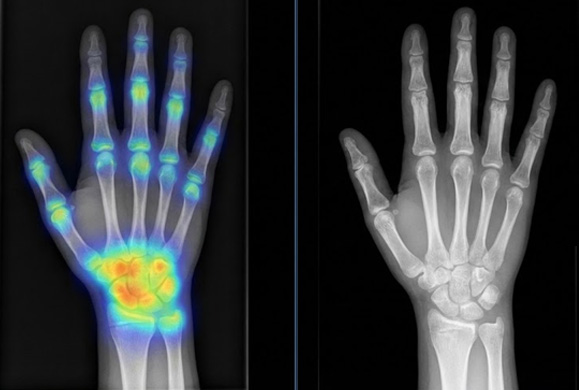

손 X-ray 기반 AI 골연령 분석으로 성장판 상태를 확인하고, 최종키 예측까지 수치로 계산합니다.

“대충”이 아니라 AI 기반의 정량

평가로 정확한 치료 방향을

잡습니다.

손 X-ray 및 AI 분석으로

골연령을 산출하고, 이를 종합해

최종 성장 예측치를 계산합니다.